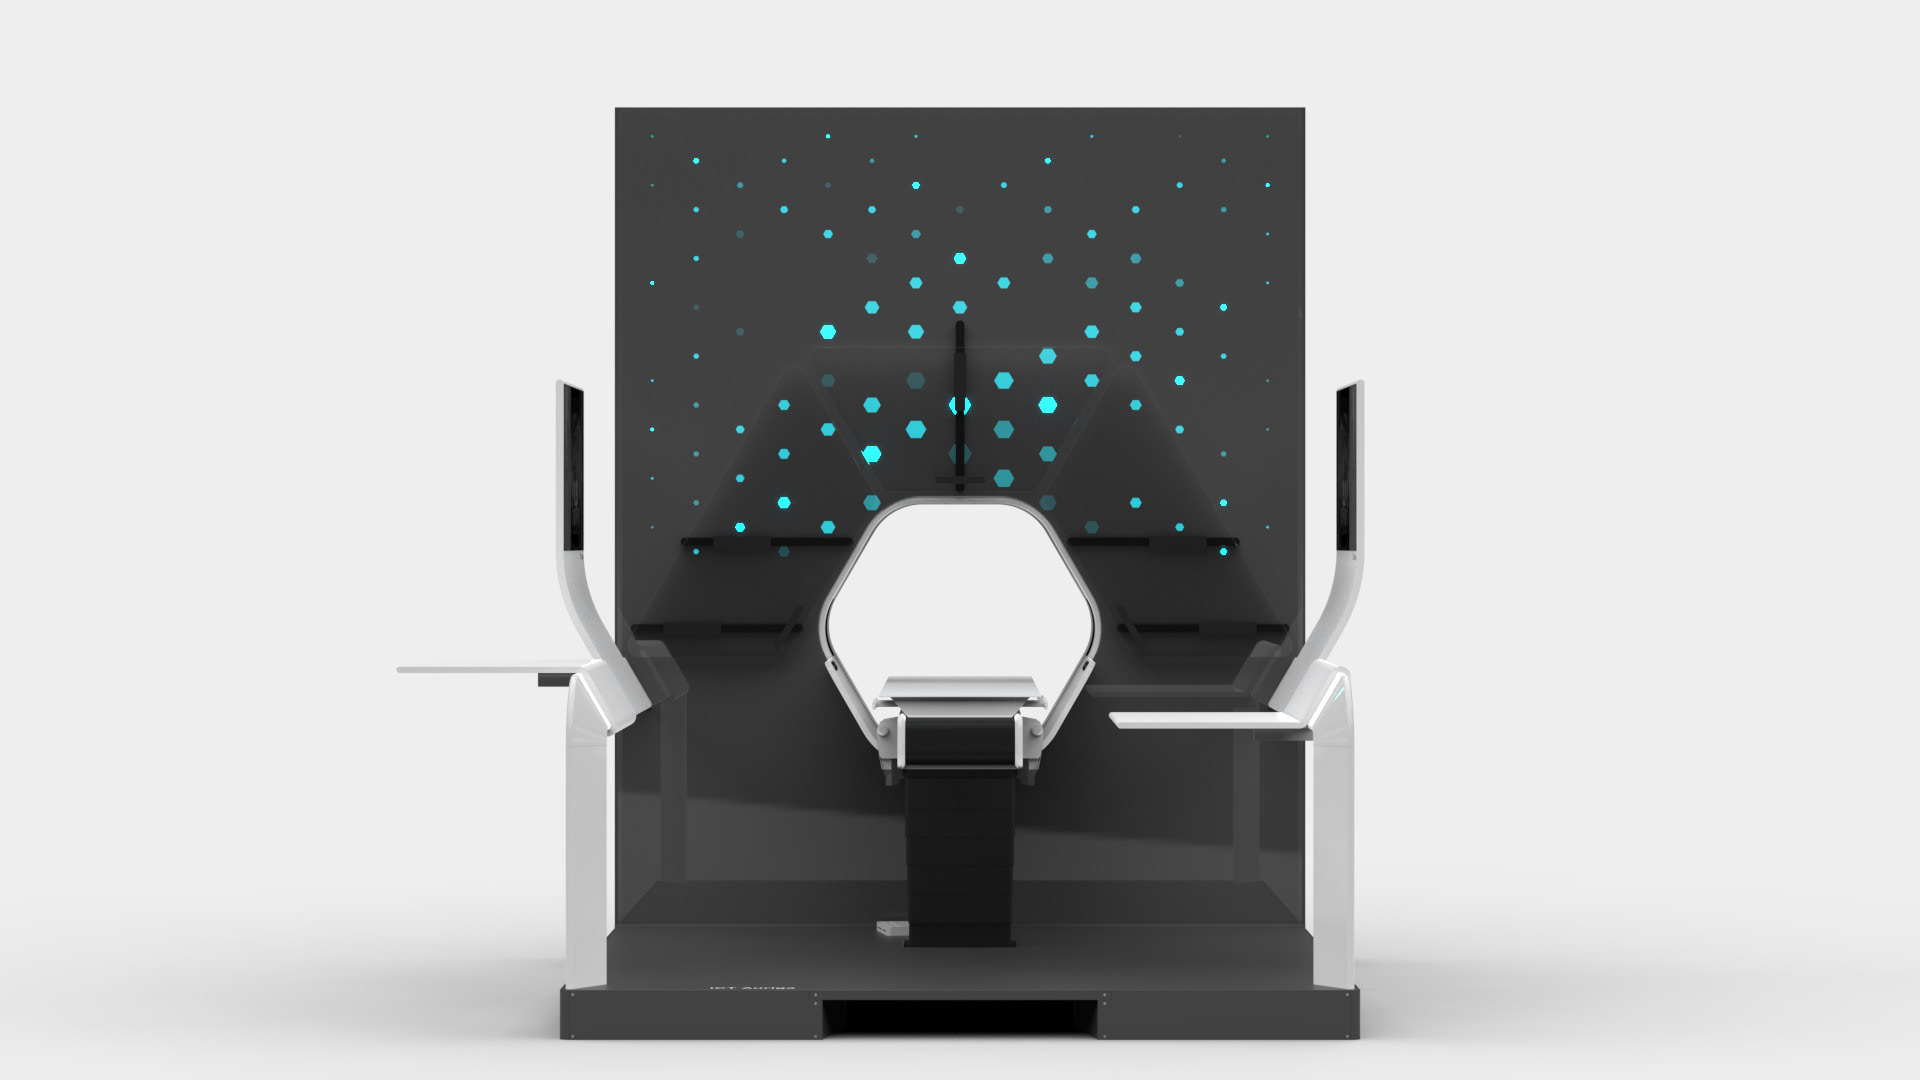

Auriga is an architecturally inspired CT device. The gantry extends to the ceiling and becomes a spatial installation. This takes away its massive “machine-character” and makes it part of the room. The gantry height is individually adapted to the given space - individuality becomes part of the product. In order to enable right- and left-handed working, the overall construction is symmetrical and intervention from both sides is equally possible.

The central design feature is the hexagonal gantry opening. It provides space for the lamps and displays. The large fronts of the gantry offer space for a display of different coloured patterns and animations, which visualize the radiation. These can be individually selected and adapted together with the overall height of the gantry. The patterns pick up on the hexagonal shape of the gantry opening and set it off. To protect the interventionists from radiation, lead glass panels and a radiation protection tray are installed. The sliding lead glass panels allow individual adaptation to the patient and the interventionists working space. The tray serves to protect the abdomen and offers a lot of foot space as well as a front leaning aid for a safe stand.

INTERFACES

For direct inspection of the CT scans, there is one large overview screen per side and a small detail screen inside the gantry. The control interface of the gantry is located inside the lower trough, which protects the abdomen of the interventionists from radiation. In addition, there is a foot pedal on the floor that allows hands-free activation of the CT imaging.

Various tables can be suspended on the railing. This enables the individual positioning of surgical instruments and devices. To relieve the interventionists, it is also possible to lean against the railing, similar to a standing seat in a gondola or tram. In addition, the railing offers protection against a potential fall from the platform.

DESIGN